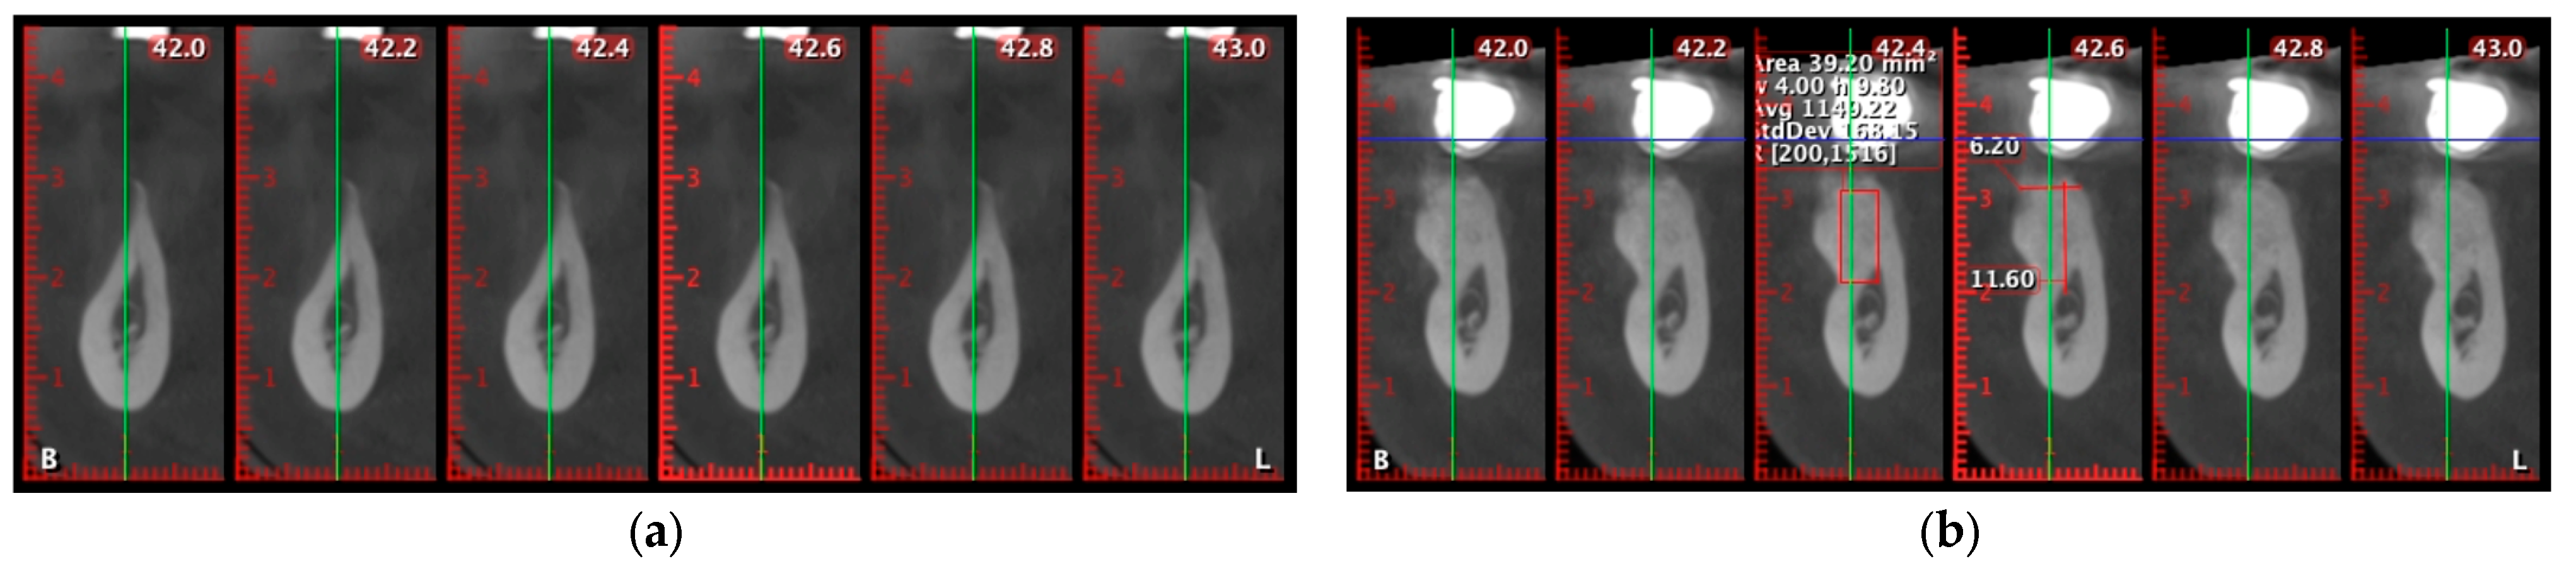

A representative case is shown in Figure 6 to illustrate the CBCT-based evaluation protocol. Cross-sectional slices between 45.2 and 46.0 mm were analyzed using the same acquisition settings and patient positioning as in all other cases. Radiographic measurements were performed by a calibrated examiner using standardized tools. This example demonstrates the methodology used to assess ridge width, trabecular density, and cortical continuity.

All scans were acquired with identical device settings and patient positioning, and all radiographic measurements were performed by a calibrated examiner as seen in Figure 7.

Cone-beam computed tomography (CBCT) analysis was used to quantitatively assess dimensional changes and bone quality at the augmentation sites. Postoperative scans at 6 months were compared to baseline images using matched cross-sectional slices, ensuring high precision in measuring ridge width and trabecular density.

In a representative case, cross-sectional evaluation was focused on the 42.4 mm slice (Figure 12). Preoperatively, the alveolar ridge presented a critical horizontal deficiency, with a width of only 1.20 mm and thin, discontinuous cortical plates. The average trabecular bone density was 777.10 HU, with values ranging from 22 to 1295 HU, indicating predominantly low-density cancellous bone (Figure 12a).

At 6 months post-augmentation, the same slice showed a ridge width of 11.63 mm, demonstrating a net horizontal bone gain of 10.43 mm. Radiographically, the area displayed continuous corticalization and homogeneous trabecular density, confirming effective mineralization of the grafted site (Figure 12b).

Figure 7. CBCT-based evaluation at 6 months postoperatively in a representative case. Cross-sectional analysis at 45.6 mm revealed a horizontal ridge width of 11.02 mm and a trabecular bone density estimated at 960 Hounsfield Units (HU). The buccal and lingual cortices were intact, with no evidence of dehiscence or fenestration. The 3D volumetric reconstruction confirmed complete bone coverage and spatial integrity around the radiopaque implant structure.

Figure 12. (a) Preoperative slice showing severe horizontal ridge deficiency (width: 1.20 mm). (b) Six-month postoperative slice showing horizontal ridge width increased to 11.63 mm and continuous corticalization, confirming successful bone regeneration and graft mineralization.